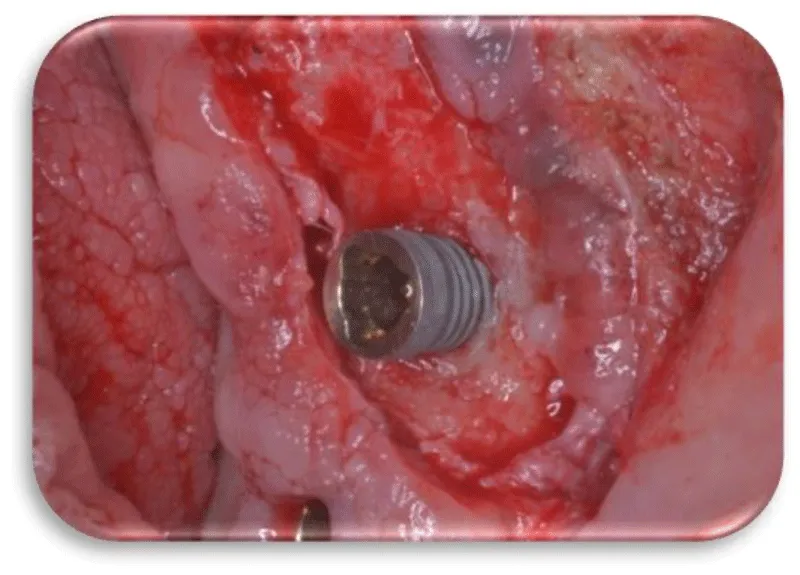

The first patient was at the age of 48 with male gender and generally with good health. There are no contraindications to make oral surgery. The patient is not allergic to any medication. A dental implant was placed 12 months ago (Figures 11,12), the dental implant’s position was 46. The implant was 4.1 mm in diameter and 12 mm in length. The patient has peri-implantitis, a RTG intraoral radiography image was recorded and marginal bone resorption was observed. The depth of the gingival sulcus was 10mm. Dehiscencia was seen in the patient from the buccal side of the implant (Figure 13). The bone defect was closed with a bone graft (Figures 14-16).

Before placing the dental implants, it is necessary to take an exhaustive history of the patient, to make the diagnosis and the plan of therapy. The procedure for implanting a dental implant involves first giving a local anesthetic a scalpel of size 15 and taking a sulcus incision, the buccal length of the implant site, and a vertical relaxation incision to protect the adjacent papilla. Before the initial osteotomy, we approach which measurement of the diameter of the alveolus and we estimate its architecture using special depth lines. Initial osteotomy is performed with the help of special borers. When doing osteotomy, we should pay attention to the depth due to the restorative platform that should not be deeper than 2-3mm apical from the cement enamel boundary of the future final restoration. Placement of the implant is carried out with a torsion force of 30Ncm. The first suture is set for the correct positioning of the cortical margin of the lamp using a thread for sutures of 5-0 or lower. After 7-10 days the strings are removed. After the completed modeling and soft tissue formation around the implant, the definitive restoration is made. Once the implant is placed in the bone, after a certain period the phase of their association, i.e. osteointegration and fibrous integration, is followed. After the osteointegration of the implants, the opening of the buried implants, mounting of the abutment and preparation of a prosthetic superstructure is followed. After the selection of the suprastructure, we approach the fingerprint for the working model, the prosthetic compensation is made and the definitive setting of the suprastructure and the prostitution fee follows [1].